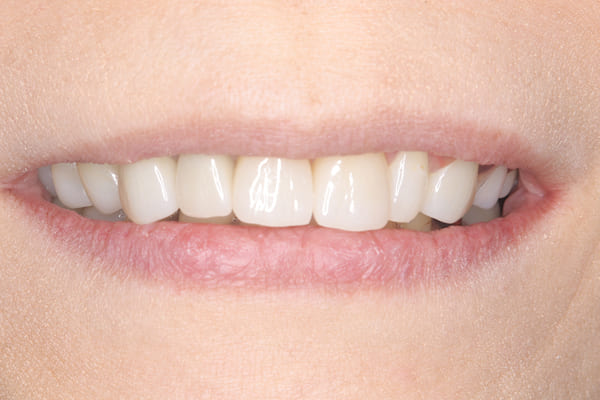

治療前後の口元の比較

こちらは、口を少し開いた時の治療前と治療後の

口元です。

正面から見た時にクラスプが目立たないように、

歯ぐきになじむ素材にて入れ歯を製作し、痛くなく自然に馴染み快適に生活を送れるようになりました。